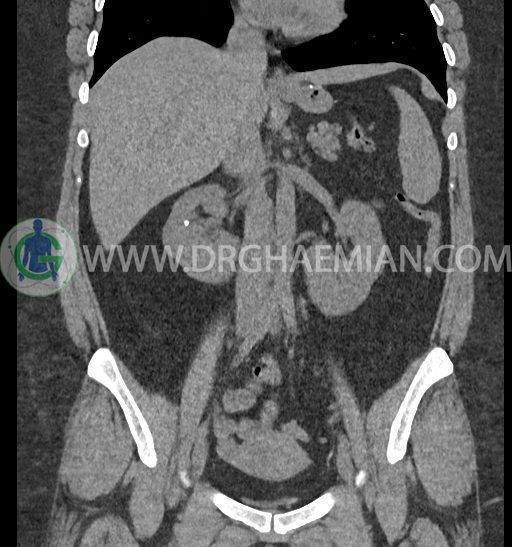

سی تی اسکن شکم و لگن با استفاده از اشعات ایکس تصاویر عرضی از ناحیه شکم و لگن ایجاد میکند. در این کیس کلیه نعل اسبی و سنگ کلیه مشاهده می شود.

در سی تی اسکن اسپیرال شکم و لگن بدون کنتراست (مولتی دیدکتور 16 با مقاطع ظریف و بازسازی های ساژیتال و کرونال) :

-horseshoe kidney

-حداقل سه سنگ 5mm در کلیه راست و یک سنگ 3mm در کلیه چپ بدون شواهدی از هیدرونفروز